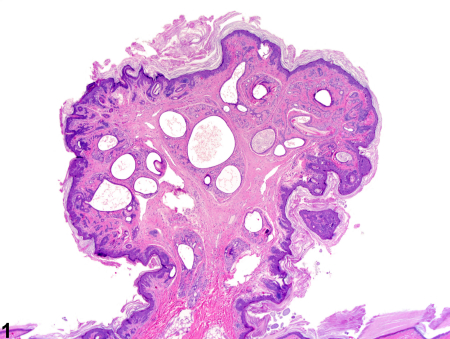

هامارتوما یک تومور غیرسرطانی (خوش‌خیم) است که از همان سلول‌های موجود در بافت اطراف ساخته شده است، اما این سلول‌ها و بافت‌ها به صورت نامنظم و بی‌نظم تومور می‌کنند. بیشتر هامارتوماها هیچ علامتی ایجاد نمی‌کنند و جدی نیستند. اگر هامارتوما مشکلی ایجاد کند، معمولاً با جراحی برطرف می‌شود.

هامارتوما (تلفظ: هَم-آر-تُو-ما) یک تومور شبه‌توموری است که می‌تواند در هر جای بدن ظاهر شود. وقتی مردم کلمه «تومور» را می‌شنوند، اغلب به سرطان فکر می‌کنند، اما هامارتوماها سرطان نیستند. آن‌ها فقط ترکیبی از همان سلول‌ها و بافت‌هایی هستند که به طور طبیعی در آن ناحیه از بدن وجود دارند، اما به صورت نامنظم تومور کرده‌اند.

تشخیص

هامارتوماها اغلب به طور اتفاقی در تصویربرداری برای مشکل دیگری کشف می‌شوند. برای تأیید تشخیص ممکن است نیاز به آزمایش‌های تصویربرداری زیر باشد:

در صورت شک به سرطان، ممکن است بیوپسی (نمونه‌برداری) انجام شود.